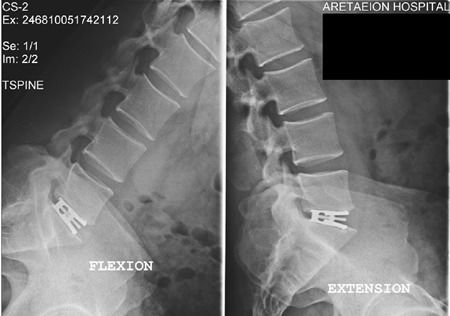

Especially in cases of lumbar disc herniation relapse or first grade spondylolisthesis it has been shown that the mini Interbody fusion is the final solution. More specifically and with posterior lumbar access a bone window is created without requiring laminectomy to allow access for removal of the corpus ligament, fat and herniated disc and then two expandable cages are implanted intervertebrally which ensure both stabilization – fusion and prevent prolapse of disc into the inner foramen or spinal canal.

The outer surfaces of these cages are coated with hydroxyapatite material that promotes synostosis with the vertebral bodies.